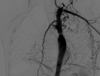

Diagnóstico de coartación aórtica

* Angiografía * AngioTC * AngioRM

Coartación aórtica

150